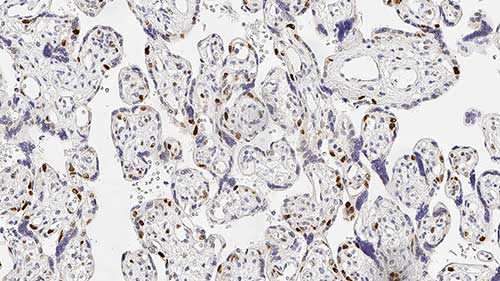

Human placenta: immunohistochemical staining for p57 protein. Note nuclear staining for cytotrophoblast and stromal cells of the villi. p57: clone 25B2

Cyclin-dependent kinases are positive regulators of cell proliferation. p57 protein acts as a tumor suppressor to counter this. It is closely related to other CDKIs such as p21 protein (CIP1) and p27 protein (Kip1) as they share a common structural N-terminal domain for binding to CDK/cyclin complexes and inhibiting their kinase activity. Human p57 protein is found on chromosome 11p15.5, a region which is reported to be a common site for loss of heterozygosity in certain sarcomas, Wilms’ tumors and tumors associated with the Beckwith-Wiedermann syndrome. There is increasing interest in p57 as a marker in gestational disease. Gestational trophoblastic disease refers to a spectrum of proliferative disorders of the placental trophoblast, with a wide range of histologic appearances and clinical behaviors. Recent development in changes in the criteria for histologic diagnosis of these lesions due to earlier clinical diagnosis have been reviewed (Hui P et al., Advantages in Anatomical Pathology. 12(3): 116-125) (2005) and the ability to make more accurate diagnoses due to the introduction of newer antibodies such as p57 is discussed.